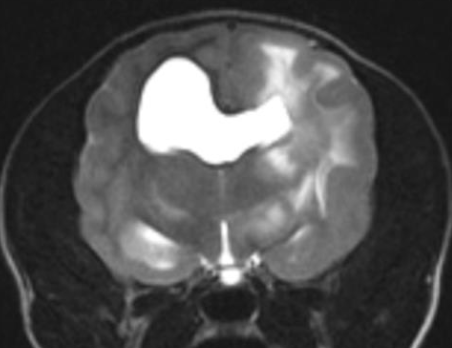

Figur 1. T2W dorsal MRI bild visar av en Fransk bulldog med en neoplastisk förändring, sannolikt ett gliom, i vänster frontallob.

Figur 2. Transversal DT bild av en ung chihuahua med grav hydrocefalus

Figur 3. T2W transversal MRI bild av en chihuahua med meningoencefalit av okänd etiologi (MUE)